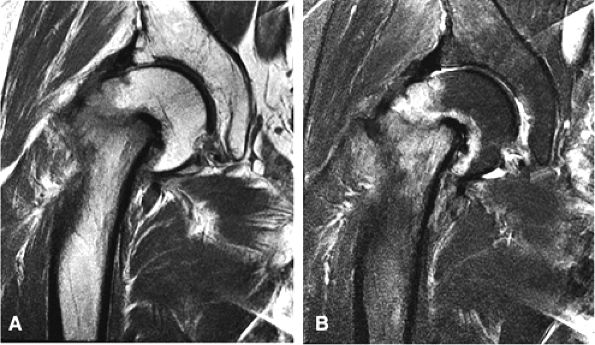

FIGURE 3.97 ● Transient osteoporosis of the hip with partial marrow-sparing of the greater trochanter and medial femoral head. No subchondral fracture is identified. (A) Coronal color section. (B) Coronal T1-weighted image. (C) Coronal FS PD FSE image.

Most cases actually represent subchondral femoral head stress fractures, which can be appreciated on small-FOV images.

There is marrow sparing in the medial femoral head and greater trochanter.

Diffuse or large areas of hypointensity within the femoral head and neck, sometimes extending to the intertrochanteric region and/or the acetabulum

A homogeneous and well-marginated edema pattern

There may be marrow sparing in the medial and lateral-most margins of the femoral head and greater trochanter secondary to higher concentrations of fatty marrow.

Resolution is associated with web-like or reticular areas of hypointensity.